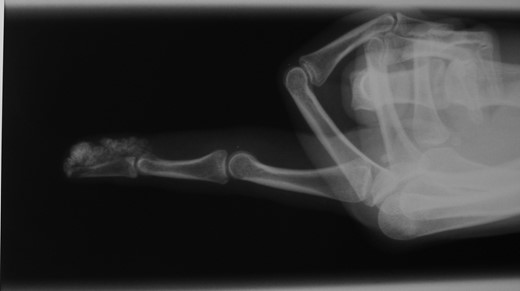

A 22-year-old woman, right dominant hand, visited our Department complaining of the presence of several small swellings localized under the skin of the pulp of the index finger (Figs 1–5). She reported an increase in the number of swellings in a period of about 2 years. She noted the first one 3 years before. She never felt pain. An X-ray of the index finger showed multiple not well-defined round-like calcified lesions, without involvement of the bone or of the distal interphalangeal joint. There were no other such lesions in the body. The patient was apyrexial and in good general health. There were no signs of tenosynovitis, palmar space or flexor sheath infection. She had no lymphangitis or regional lymphadenopathy.